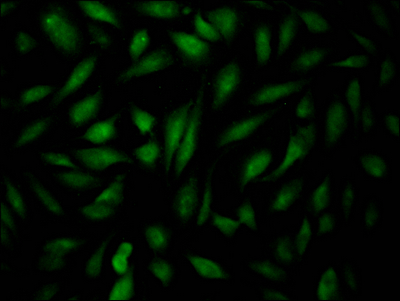

• Immunofluorescence staining of Hela Cells with CSB-RA904931A0HU at 1:50, counter-stained with DAPI. The cells were fixed in 4% formaldehyde, permeated by 0.2% TritonX-100, and blocked in 10% normal Goat Serum. The cells were then incubated with the antibody overnight at 4℃. Nuclear DNA was labeled in blue with DAPI. The secondary antibody was FITC-conjugated AffiniPure Goat Anti-Rabbit IgG (H+L).